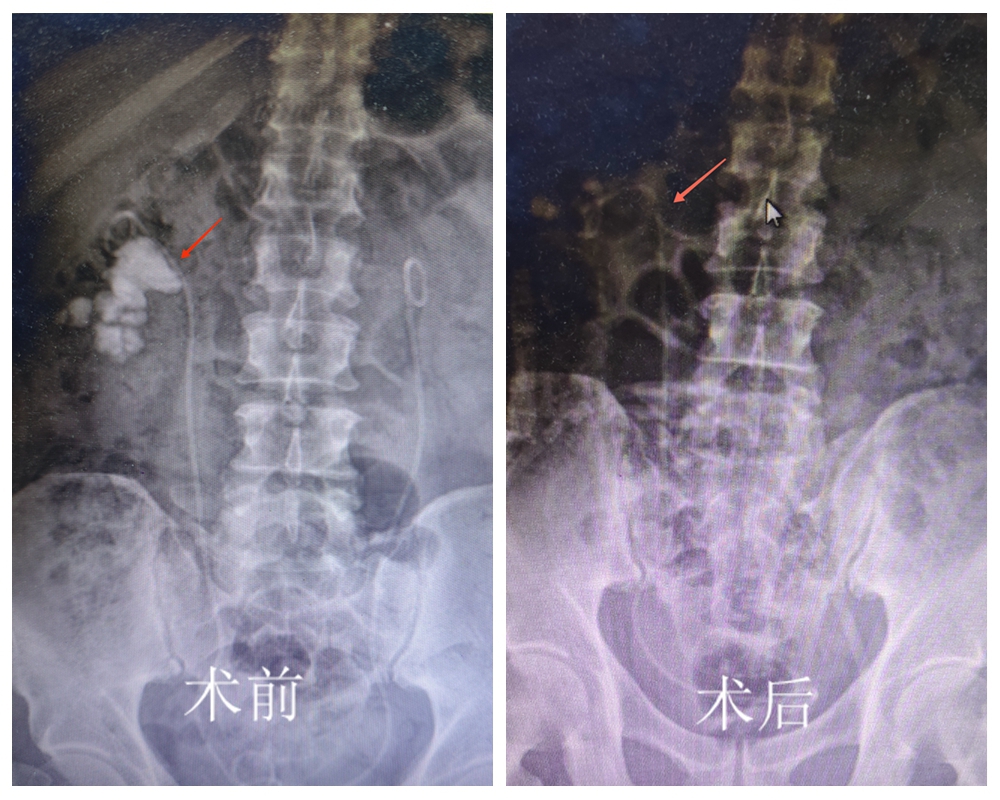

一月后,患者再次入院需接受右侧孤立肾经皮肾镜激光碎石术。由于手术风险极大,科室详细告知相关风险并建议转诊上级医院,但患者及家属基于对医院的充分信任,坚持留在该院接受手术。面对患者的信任,医疗团队进行了充分的术前准备,制定多套应急预案,最终手术历时近三小时获得成功。术后患者未出现并发症,肾功能逐步稳定。